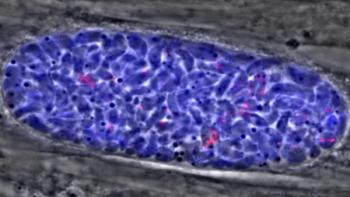

One in three people has a potentially nasty parasite hiding inside their body -- tucked away in tiny cysts that the immune system can’t eliminate and antibiotics can’t touch. But new research reveals clues about how to stop it: Interfere with its digestion during this stubborn dormant phase. If the discovery, made at the University of Michigan, leads to new treatments, it could help prevent a parasitic disease called toxoplasmosis that sickens people worldwide. For many people, the parasite Toxoplasma gondii only causes mild flu-like symptoms, often from food poisoning. After that initial infection, it usually goes into cyst phase and remains in the person’s body for the rest of their life.